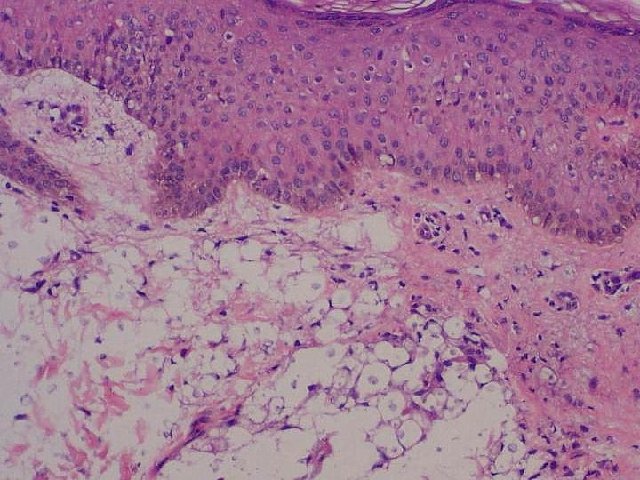

DERMATOHISTOPATHOLOGY:

His skin biopsy revealed numerous organisms of various sizes surrounded by capsules, which stained positive with mucicarmine in the superficial and deep dermis, with very little inflammatory response. (Fig 3,4)

Fig3. H & E stain of 3mm punch biopsy at 10X showing numerous encapsulated organisms in the superficial and deep dermis with very little inflammatory response